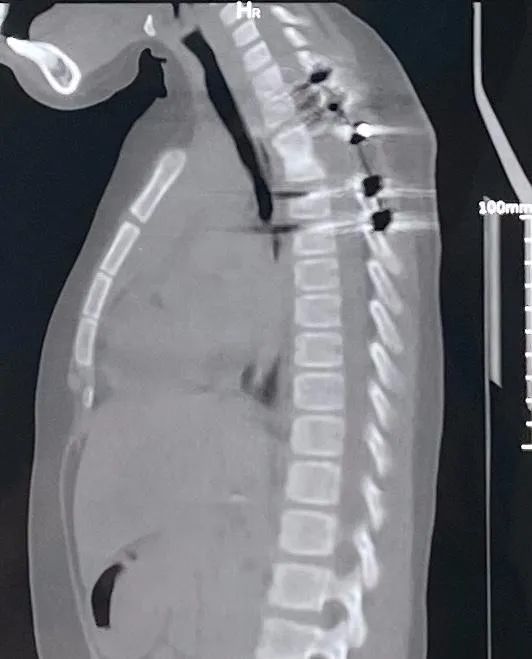

▶ 手术前,第2,3胸椎结核,大量死骨、脓液,脊柱后凸,压迫脊髓

入院后第3天,谢宁主任带领王建杰和任亦龙主治医生实施了胸椎结核病灶清除重建手术,清除了死骨和脓液,手术中见到胸主动脉和脊髓都泡在脓液内,血管破裂会危及生命,十分凶险。考虑到病儿以后要生长发育,尽可能减少对其他部位骨头的干扰,利用剪下的肋骨作支撑,顺利完成植骨固定。护理和康复的姐姐们用玩具、贴纸哄小朋友吃药,做康复训练,病儿一家顺利地在除夕夜回到家乡。

▶ 手术后11个月,胸椎结核治愈,后凸矫正,植骨融合